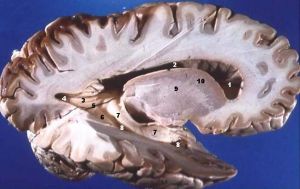

脑白质是中枢神经系统中主要的三个组成元素之一,与灰质、黑质并列。大脑剖面中的白质组织是由大量的髓磷脂(脂质)组成,在裸视观察下呈现白色。白质由被髓鞘包覆著的神经轴突组成,控制着神经元共享的讯号,协调脑区之间的正常运作。

现在科学家利用一种新的造影技术观察人类的脑部,其中白质几乎填满了半个大脑。白质由数百万条“沟通管线”组成,管线里包覆著一根长长的轴突(又称突起),管线外包覆著称为髓磷脂的白色脂质,而这些“白色缆线”的功能是负责沟通不同脑区的灰质(神经元)、在神经元间传递动作电位。